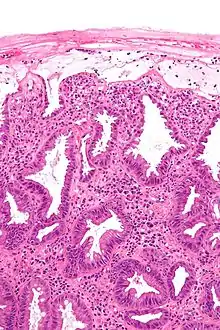

![]() صورة مجهرية تظهر التغيرات التي ترى في التهاب القولون لنقص التروية. صبغة H&E. صورة مجهرية تظهر التغيرات التي ترى في التهاب القولون لنقص التروية. صبغة H&E. | |